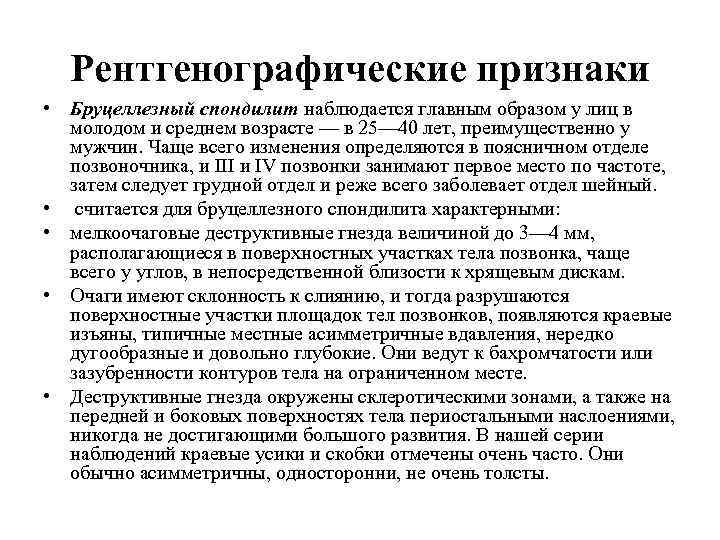

Рентгенографические признаки • Бруцеллезный спондилит наблюдается главным образом у лиц в молодом и среднем возрасте — в 25— 40 лет, преимущественно у мужчин. Чаще всего изменения определяются в поясничном отделе позвоночника, и III и IV позвонки занимают первое место по частоте, затем следует грудной отдел и реже всего заболевает отдел шейный. • считается для бруцеллезного спондилита характерными: • мелкоочаговые деструктивные гнезда величиной до 3— 4 мм, располагающиеся в поверхностных участках тела позвонка, чаще всего у углов, в непосредственной близости к хрящевым дискам. • Очаги имеют склонность к слиянию, и тогда разрушаются поверхностные участки площадок тел позвонков, появляются краевые изъяны, типичные местные асимметричные вдавления, нередко дугообразные и довольно глубокие. Они ведут к бахромчатости или зазубренности контуров тела на ограниченном месте. • Деструктивные гнезда окружены склеротическими зонами, а также на передней и боковых поверхностях тела периостальными наслоениями, никогда не достигающими большого развития. В нашей серии наблюдений краевые усики и скобки отмечены очень часто. Они обычно асимметричны, односторонни, не очень толсты.

Рентгенографические признаки • Бруцеллезный спондилит наблюдается главным образом у лиц в молодом и среднем возрасте — в 25— 40 лет, преимущественно у мужчин. Чаще всего изменения определяются в поясничном отделе позвоночника, и III и IV позвонки занимают первое место по частоте, затем следует грудной отдел и реже всего заболевает отдел шейный. • считается для бруцеллезного спондилита характерными: • мелкоочаговые деструктивные гнезда величиной до 3— 4 мм, располагающиеся в поверхностных участках тела позвонка, чаще всего у углов, в непосредственной близости к хрящевым дискам. • Очаги имеют склонность к слиянию, и тогда разрушаются поверхностные участки площадок тел позвонков, появляются краевые изъяны, типичные местные асимметричные вдавления, нередко дугообразные и довольно глубокие. Они ведут к бахромчатости или зазубренности контуров тела на ограниченном месте. • Деструктивные гнезда окружены склеротическими зонами, а также на передней и боковых поверхностях тела периостальными наслоениями, никогда не достигающими большого развития. В нашей серии наблюдений краевые усики и скобки отмечены очень часто. Они обычно асимметричны, односторонни, не очень толсты.